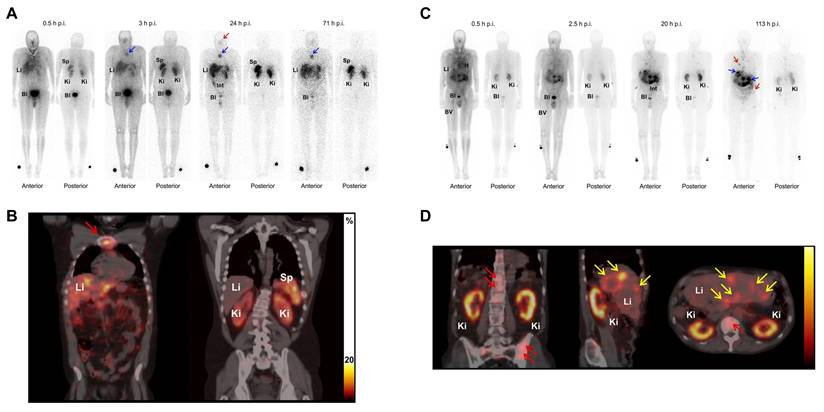

[161Tb]Tb-[161Tb]Tb-DOTATOCSSTR-2/5Patient with paraganglioma (metastatic, well-differentiated, nonfunctional malignant) and neuroendocrine neoplasm of pancreas tail (metastatic, functional)A first-in-human study demonstrated that [161Tb]Tb-DOTATOC, synthesized with high radiochemical purity, enabled high-quality SPECT/CT imaging and detection of small bone and liver metastases at low administered activities, showing favorable biodistribution in the liver, kidneys, spleen, and bladder without any reported adverse effects.[177]

[161Tb]Tb-DOTATATESSTR-2Patients with NET (SSTR positive)Substitution of [177Lu]Lu- with [161Tb]Tb-DOTATATE Therapy boosts tumor absorbed dose per administered activity by approximately 40% (e.g., 2.9 → 4.1 Gy/GBq for a 10 g tumor), but to avoid increased kidney and bone marrow toxicity, the standard 7.4 GBq administered activity should be reduced to 5.3-5.4 GBq of [161Tb]Tb-DOTATATE.[178]

[161Tb]Tb-DOTA-cm09FRHuman nasopharyngeal/ovarian cancer cell line (KB/IGROV-1) with FR-positive[161Tb]Tb-DOTA-cm09 showed superior therapeutic efficacy than [177Lu]Lu-DOTA-cm09 both in vitro and in vivo, requiring significantly lower IC50 values in FR-positive tumor cells and delivering a higher tumor dose per administered activity (3.3 Gy/MBq vs. 2.4 Gy/MBq), while maintaining imaging capabilities and renal safety over a 6-month observation period.[179]

[161Tb]Tb-SibuDABPSMA (High affinity with albumin)Human prostate cancer with PSMA-positive (PC3-PIP)Compared to [177Lu]Lu- counterparts, [161Tb]Tb-SibuDAB and PSMA-I&T exhibited similar biodistribution but provided ~ 40% higher tumor-administered activities, with [161Tb]Tb-SibuDAB showing markedly enhanced tumor uptake (up to 69% IA/g) and therapeutic efficacy without observable toxicity in mice.[180]

Patients with mCRPC[161Tb]Tb-SibuDAB achieved superior tumor retention and absorbed dose per administered activity delivery (6.5 Gy/GBq, Th = 135 h) compared with [177Lu]Lu-PSMA-I&T (2.6 Gy/GBq, Th = 67 h) in the first mCRPC patient, with no acute toxicity despite modestly higher kidney (2.6 vs. 1.2 Gy/GBq) and parotid (0.5 vs. 0.3 Gy/GBq) absorbed doses administered activities (PROGNOSTIC Phase I clinical trial, NCT06343038).[181]

[161Tb]Tb-PSMA-617PSMA6 patients with mCRPC[161Tb]Tb-PSMA-617 showed superior efficacy in mCRPC patients, with a 2.4-fold increase in tumor absorbed dose per administered activity (6.10 ± 6.59 vs. 2.59 ± 3.30 Gy/GBq) and higher therapeutic indices for the kidneys (11.54 ± 9.74 vs. 5.28 ± 5.13 Gy/GBq) and parotid glands (16.77 ± 13.10 vs. 12.51 ± 18.09 Gy/GBq) (NCT04833517).[182]

[161Tb]Tb-DOTA-LM3SSTR-2Rat pancreas tumor cell line with SSTR-positive (AR42J)Dual-isotope SPECT/CT imaging in AR42J tumor-bearing mice demonstrated that [161Tb]Tb- and [177Lu]Lu-labeled somatostatin analogues (DOTATOC and DOTA-LM3) exhibited indistinguishable PK and sub-organ biodistribution, with DOTA-LM3 showing significantly higher tumor uptake than DOTATOC (e.g., > 20% IA/g vs. ~10% IA/g at 4 h post-injection).[183]

Patient with ileal NET (metastatic, hormone-active [carcinoid syndrome])Following administration of 1 GBq [161Tb]Tb-DOTA-LM3, the patient's liver metastases demonstrated a tumor half-life of 130 h and an absorbed dose per administered activity of up to 39 Gy/GBq, while bone marrow, kidney, and spleen absorbed doses per administered activity were 0.31, 3.33, and 6.86 Gy/GBq, respectively, accompanied by a chromogranin A decrease of 163 µg/L and minimal hematologic toxicity (NCT05359146).[184]